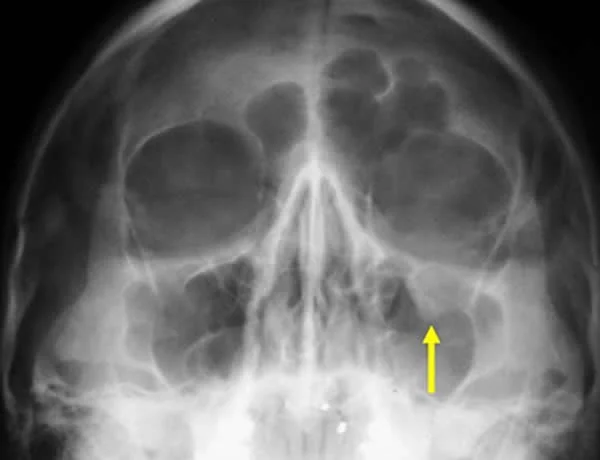

Left/Right Orbital Cellulitis

Can be from Paranasal sinusitis

Common cause:

- Sinusitis

Complications:

- Brain Abscess

- Infection spread to brain

- Cavernous Sinus Thrombosis

- vision loss

- Subperiosteal or Orbital Abscess

Investigations: (to exclude orbital causes - tumors, abscess…)

- CT with contrast